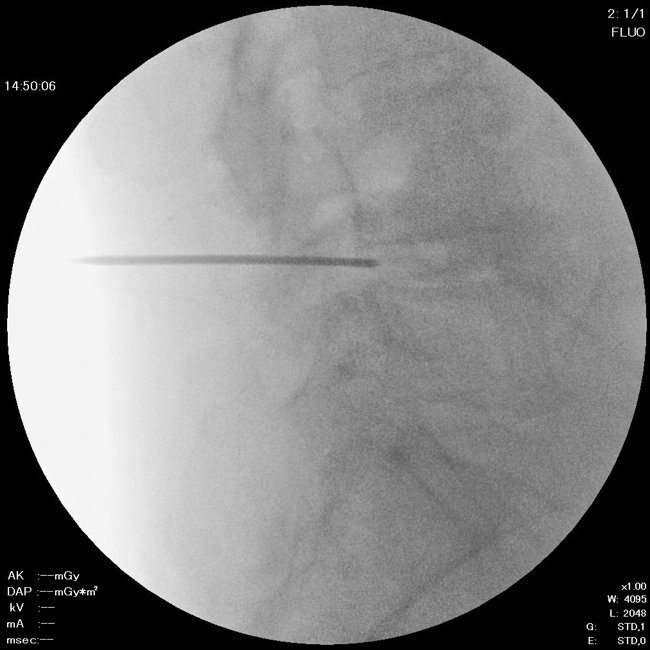

2. ニードル留置

直径約2mmのニードルを椎間板に留置します。

DISC-FX®はDART®よりも太いデバイスのため、やや大きいヘルニアに適しています。頚椎ヘルニアの場合にはDARTが選択されます。